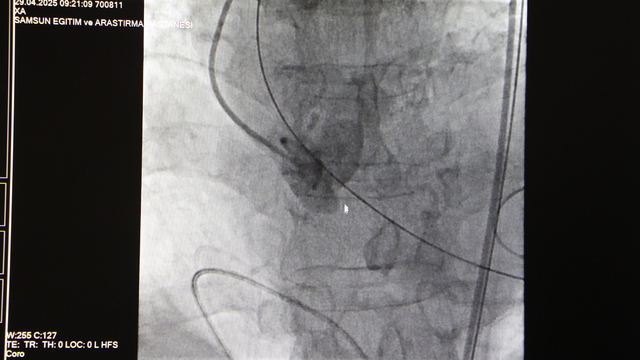

SAMSUN Eğitim ve Araştırma Hastanesi'nde 4 yaprakçıklı aort kapağı olan 80 yaşındaki Muzaffer Uslu, TAVI (Transcatheter Aortic Valve Implantation) yöntemi ile ameliyat edildi. Başarılı geçen operasyonla ilgili bilgi veren Doç. Dr. Mustafa Yenerçağ, "Hastamızın normalde aort kapağının 3 yaprakçıklı olmasını beklerken, çok çok nadir gözüken 4 yaprakçıklı bir aort kapağı olduğunu saptadık. Literatürde ülkemizde bildirilmiş bir vaka yoktu. Fakat uluslararası literatürlere baktığımızda bu yaşta 4 yaprakçıklı ve TAVİ işleminin yapıldığı 17 hastanın olduğunu gördük. Ortak bir ekiple TAVI işlemini yapmaya karar verdik. TAVI yöntemiyle kalp kapağını değiştirdik" dedi.

Amasya'nın Merzifon ilçesinde yaşayan Muzaffer Uslu, nefes darlığı ve bayılma şikayeti ile 21 Nisan'da Merzifon Devlet Hastanesi'ne başvurdu. Uslu, aort kapağının ileri düzeyde daralması nedeniyle 23 Nisan'da Samsun Eğitim ve Araştırma Hastanesi’ne sevk edildi. Burada Samsun Üniversitesi Tıp Fakültesi Kardiyoloji ve Anabilim Dalı Öğretim Üyesi Doç. Dr. Mustafa Yenerçağ ile alanında uzman doktorlar, TAVI (Transcatheter Aortic Valve Implantation) yöntemi ile ameliyat yapılmasına karar verdi. Hasta Muzaffer Uslu, 29 Nisan'da ameliyata alındı. 50 dakika süren ameliyatın ardından hasta Uslu, 1 gün yoğun bakım kaldı ve servise alındı.

Doç. Dr. Yenerçağ, "Bu konuda iyice hazırlandık. Bu konuda deneyimli hocalarımızdan da bilgi aldık. Sonrasında hastamıza Doç. Dr. Serkan Sivri, ben, asistanlarımdan Dr. Berkant Öztürk ve Dr. Enes Kaya ile beraber ayrıca anesteziden de Uzm. Dr. Aynur Kaynar hocamızla beraber ortak bir ekiple TAVI işlemini yapmaya karar verdik ve 2 gün önce hastamıza başarılı bir şekilde sağ kasığından girerek genel anestezi vermeden başarılı bir şekilde kalp kapağını değiştirdik. TAVI yöntemiyle kalp kapağını değiştirdik. İşlemimiz gayet başarılı geçti. 1 gün yoğun bakımda hastamızı takip ettik. 1 gündür de servise takip ediyoruz. Bir aksilik olmadığı sürece de yarın taburcu etmeyi planlıyoruz" diye konuştu.